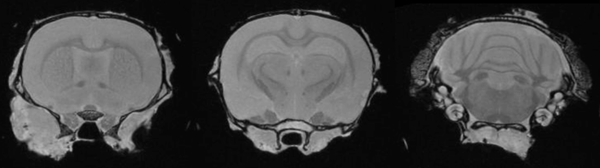

Ex-Vivo Imaging: Ex vivo imaging can produce high-resolution images of the rat brain, providing excellent delineation of brain regions. Image Credit: Scintica Instrumentation Inc

Ex vivo imaging

Excised tissues preserved in formalin can undergo MRI at a resolution far higher than a live animal's. Ex-vivo 3D MRI makes identifying and measuring lesions in entire organs or brain structures possible. It can also assist in directing additional histopathological processing and sectioning for standard pathological analysis of areas of interest.

Ex vivo imaging can produce high-resolution images of the rat brain providing excellent delineation of brain regions. Image Credit: Scintica Instrumentation Inc